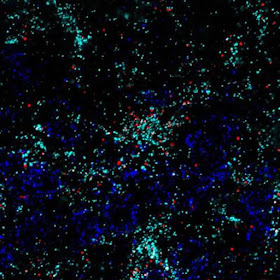

Астроциты – основные клетки мозга, которые производят Chrdl1. Благодаря методу, называемому флуоресценцией гибридицации in situ, РНК, соответствующие синтезу, различных белков помечается флуоресцентными метками. На изображении Chrdl1 показан красным цветом, астроциты голубым, а нейроны в темно-синем цвете. На снимке мы видим верхние слоях зрительной коры мыши. Сигнал от Chrdl1 перекрывается с астроцитами, но не с нейронами, что указывает на то, что астроциты являются клетками, которые в основном производят Chrdl1. Credit: Институт Солка